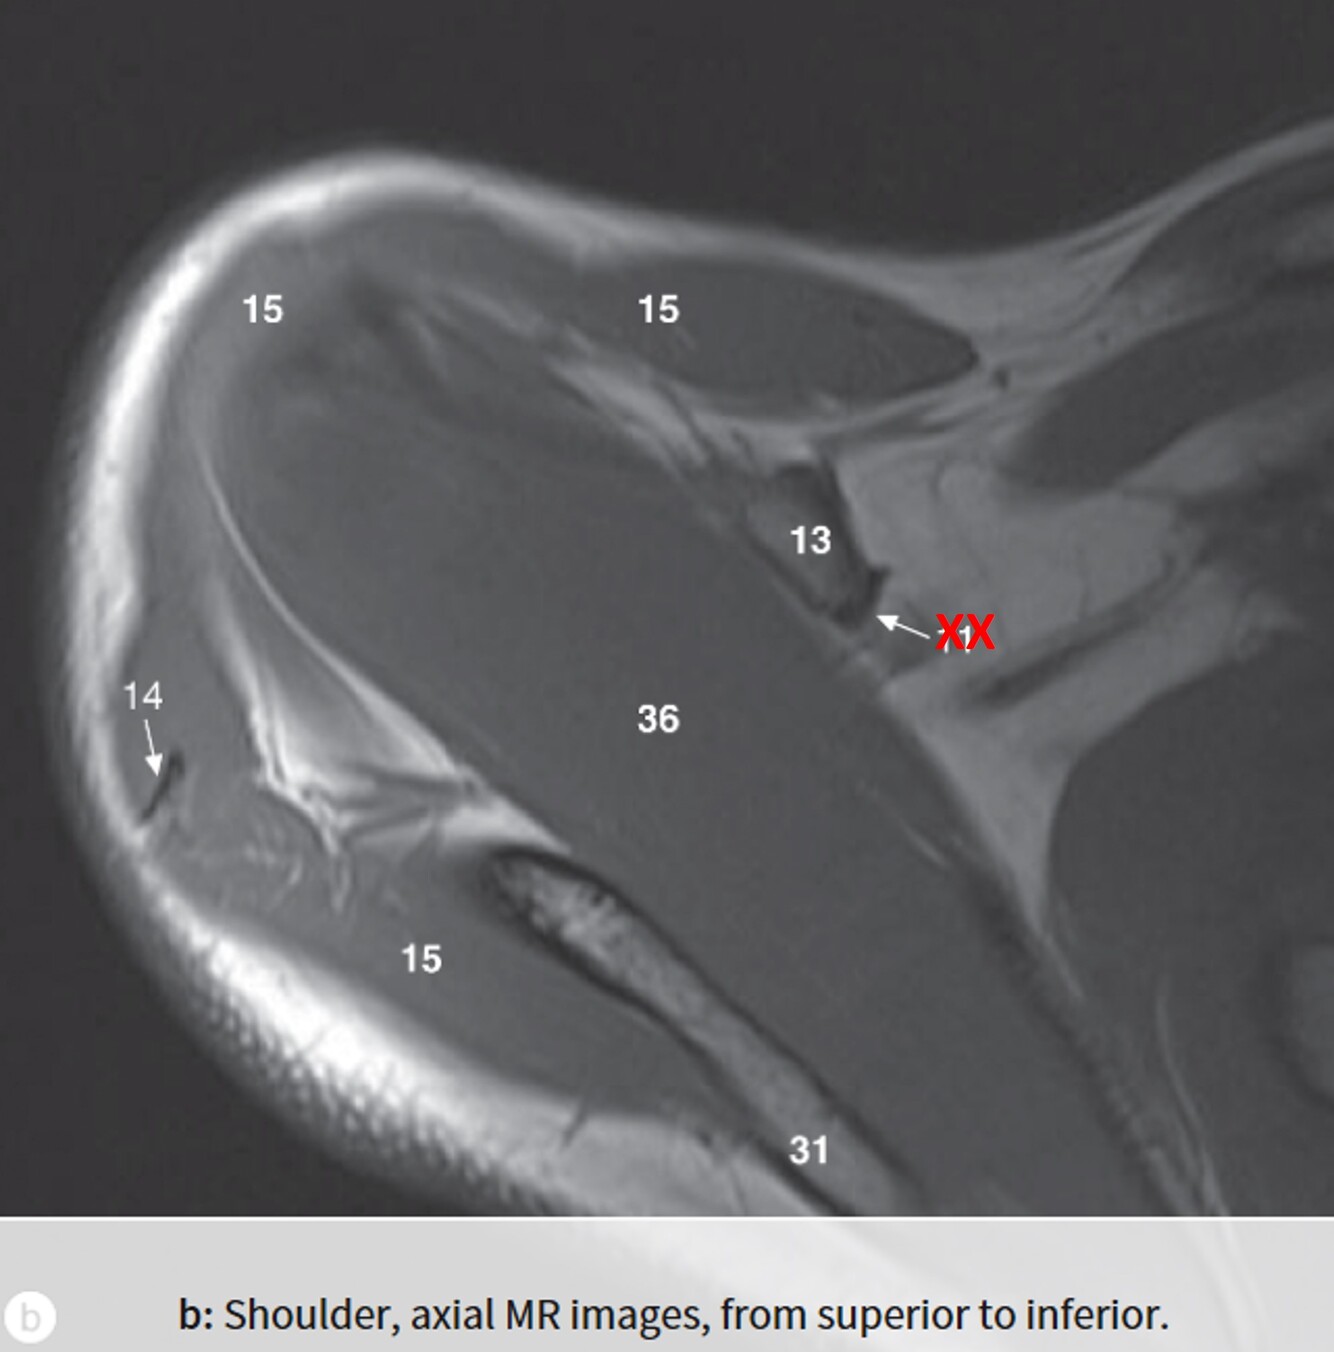

Label 31,13,15,36

31=Spine of rt. scapula

13=Coracoid process of right scapula

15=Rt. deltoid muscle

36=Rt. supraspinatus muscle

Label 1,2,9,15,16,19

1=Rt. AC joint

2=Acromion of rt. scapula

9=Rt. clavicle (acromial end)

16=Glenoid process of rt. scapula

19=Head of rt. humerus